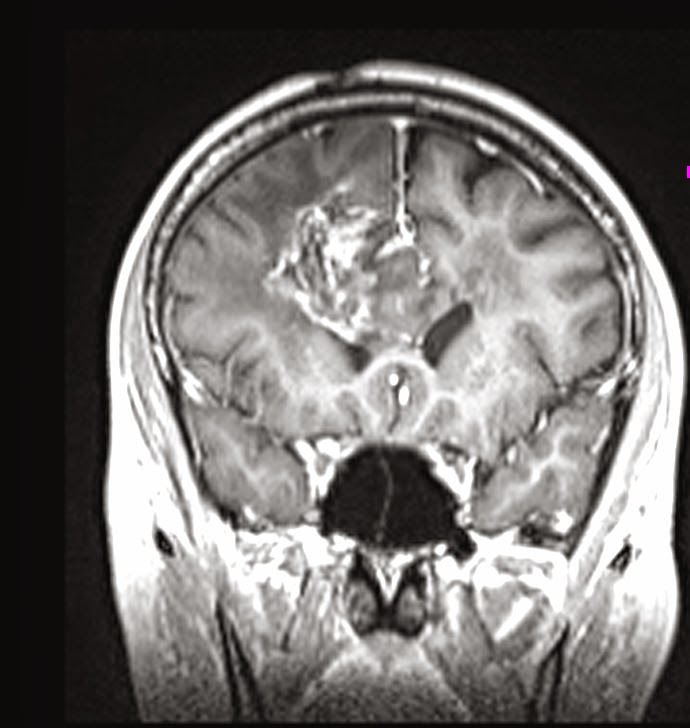

Összehasonlítva a 2014.02.10-i MR vizsgálattal:

A középvonalat balra kb. 1,5 cm-rel meghaladó és a corpus callosumot involváló jobb oldali frontalis inhomogén szerkeszetű és halmozású elváltozás mérete minden irányban mérsékelten csökkent, legnagyobb átmérője jelenleg kb. 5,6 x 5 x 4,7 cm. T2 súlyozásnál a laesio körül a hyperintenzitás kiterjedése főként dorsalis irányban enyhén csökkent. Az elülső frontalis műtéti behatolás mögött parasagittalisan a liquorhoz viszonyítva magasabb jelű bennéket tartalmazó cystosus elváltozás mérete hasonló a korábbihoz. Bal oldalon temporalis DVA* látható. A kamrarendszer frontális részeinek compressioja és dislocatioja lényegesen nem változott.

Vélemény: Enyhe méretcsökkenést mutató jobb túlsúlyú bifrontális tu. a corpus callosum infiltratiojaval.

*DVA: developmental venous anomaly (DVA) = cerebral venous angioma

Fejlődési eredetű (embrionális) vénás anomális = agyi vénás angióma (érdaganat)

Elkészült a kemoterápia alatti első MR-felvétel, és íme az eredménye:

Saját, műkedvelő fordításomban ez azt jelenti, hogy:

Jobb oldalon a corpus callosum, azaz kérgestest, amely nem más, mint a két agyféltekét összekötő rostköteg, és a gyrus cinguli, azaz az agyféltekék mediális, tehát középen elhelyezkedő felszínén található hosszú hajlított struktúra elülső részében elhelyezkedő térfoglalás nagysága érdemben nem változott, azonban a szélei jobban elhatárolódtak.

A mérsékelt fokú (hoppá! csak mérsékelt!!!) baloldali terjedés és a környező részben ödémás terület olyan, mint november 11-én volt. Az elülső és a frontális szarvak jobbra, lefelé nyomódtak össze. Továbbá az elülső szarvak hátsó fele olyan, mint volt: mérsékelten tágultak jobb túlsúllyal.

Ami jó hír: mérséklődött a középvonal balra íveltsége.

Mindazonáltal a jobb oldali árkok jobban ábrázolódnak.

A műtéti üreg a korábbihoz hasonló! Nem nőtt tovább a rohadék!!!

Az orvosi vélemény: Stabil állapot.